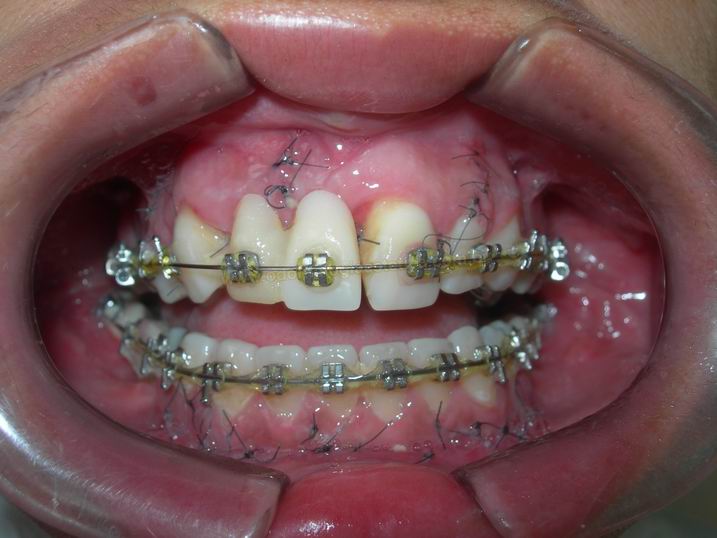

FASE INICIAL DO TRATAMENTO ORTODÕNTICO COM FIO RETANGULAR TERMOATIVÁVEL

|